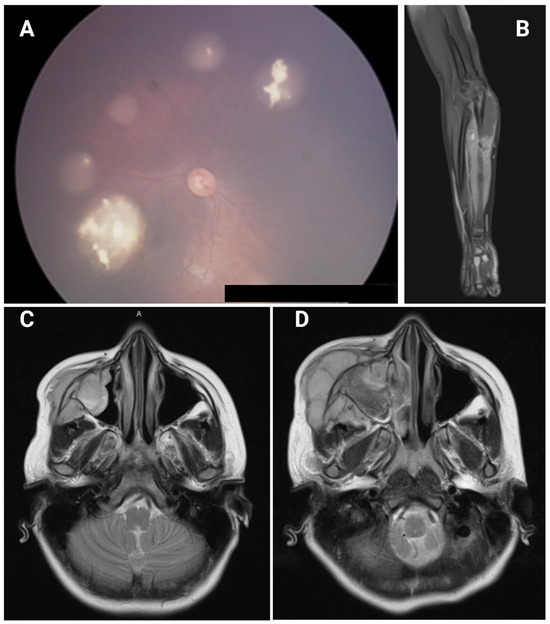

Novel RB1 and MET Gene Mutations in a Case with Bilateral Retinoblastoma Followed by Multiple Metastatic Osteosarcoma

Retinoblastoma (Rb) is a malignant tumor of the developing retina that affects children before the age of five years in association with inherited or early germline mutations of the RB1 gene. The genetic predisposition is also a driver for other primary malignancies, which have become the leading cause of death in retinoblastoma survivors. Other malignancies can occur as a consequence of radiotherapy. We describe a patient with retinoblastoma in which we detected a novel RB1 c.2548C > T, p.(Gln850Ter) and a synchronous MET c.3029C > T, p.(Thr1010Ile) mutation as well. After presenting with bilateral retinoblastoma, the patient developed at least four different manifestations of two independent osteosarcomas. Our goal was to identify all germline and somatic genetic alterations in available tissue samples from different time periods and to reconstruct their clonal relations using next generation sequencing (NGS). We also used structural and functional prediction of the mutant RB and MET proteins to find interactions between the defected proteins with potential causative role in the development of this unique form of retinoblastoma. Both histopathology and NGS findings supported the independent nature of a chondroblastic osteosarcoma of the irradiated facial bone followed by an osteoblastic sarcoma of the leg (tibia). Full article